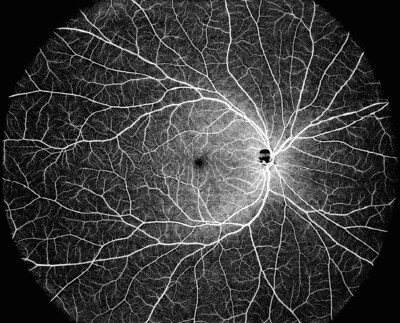

DREAM OCT ist in der Lage, ein ultraweites Feld mit einem einzigen Scan abzudecken, der ein 130°-OCTA-Bild liefert. Die 12-mm- Super-Tiefenscanfunktion von DREAM OCT™ mit Swept-Source-Technologie ermöglicht eine hervorragende Bildgebung der Aderhaut und Netzhaut sowie eines großen Teils des Glaskörperraums. Die Supertiefen- Scanfunktion für den vorderen Bereich erreicht 16,2 mm (in Luft), wodurch der gesamte vordere Bereich von der Hornhaut bis zum vorderen Teil des Glaskörpers in nur einem Scan gescannt werden kann. Die längere Wellenlänge ermöglicht eine bessere Durchdringung von Trübungen in der Linse oder im Glaskörper.

Foto – https://mma.prnewswire.com/media/2686647/Single_shot_130_... A_ID_9c4466f50527___1.jpg